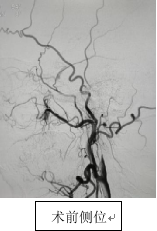

入院后,神经内科一病区王建峰主任团队迅速邀请神经外科、麻醉科及影像科等多学科举行会诊,经各项必要检查,会诊专家发现,朱先生的状况十分棘手,他的慢性闭塞血管内壁已经硬化、狭窄甚至完全堵死,状态犹如风化后的塑料薄膜,稍有外力干扰,可能会立刻崩溃。如果采用传统介入方式治疗,将极难找到通路,因此手术风险极大。

面对患者跨国就医的信任,神经内科一病区必须迎难而上,只有手术成功才能回应朱先生及家人的热切期望。在多学科会诊几番论证后,王建峰主任团队最终决定采用国内技术前沿的BASIS技术对朱先生的左侧颈部内动脉进行血管再通。

BASIS技术属于前沿技术,在陕西省的应用也相对较少,但王建峰主任团队却信心十足,长期对前沿技术与理念的应用,给了他们底气,此次手术正是利用此技术在慢性闭塞段精准建立通道的优势,通过特殊设计的取栓支架和导引方法,最大限度避免血栓脱落和脑梗加重的风险。

手术在局部麻醉下进行,王建峰主任亲自上台,操作精细,在BASIS技术辅助下,顺利通过闭塞段,成功恢复左侧颈内动脉血流。手术过程中未出现血栓脱落等并发症,术后患者生命体征平稳,已安全送回病房,在护理团队的共同努力下,朱先生恢复良好。